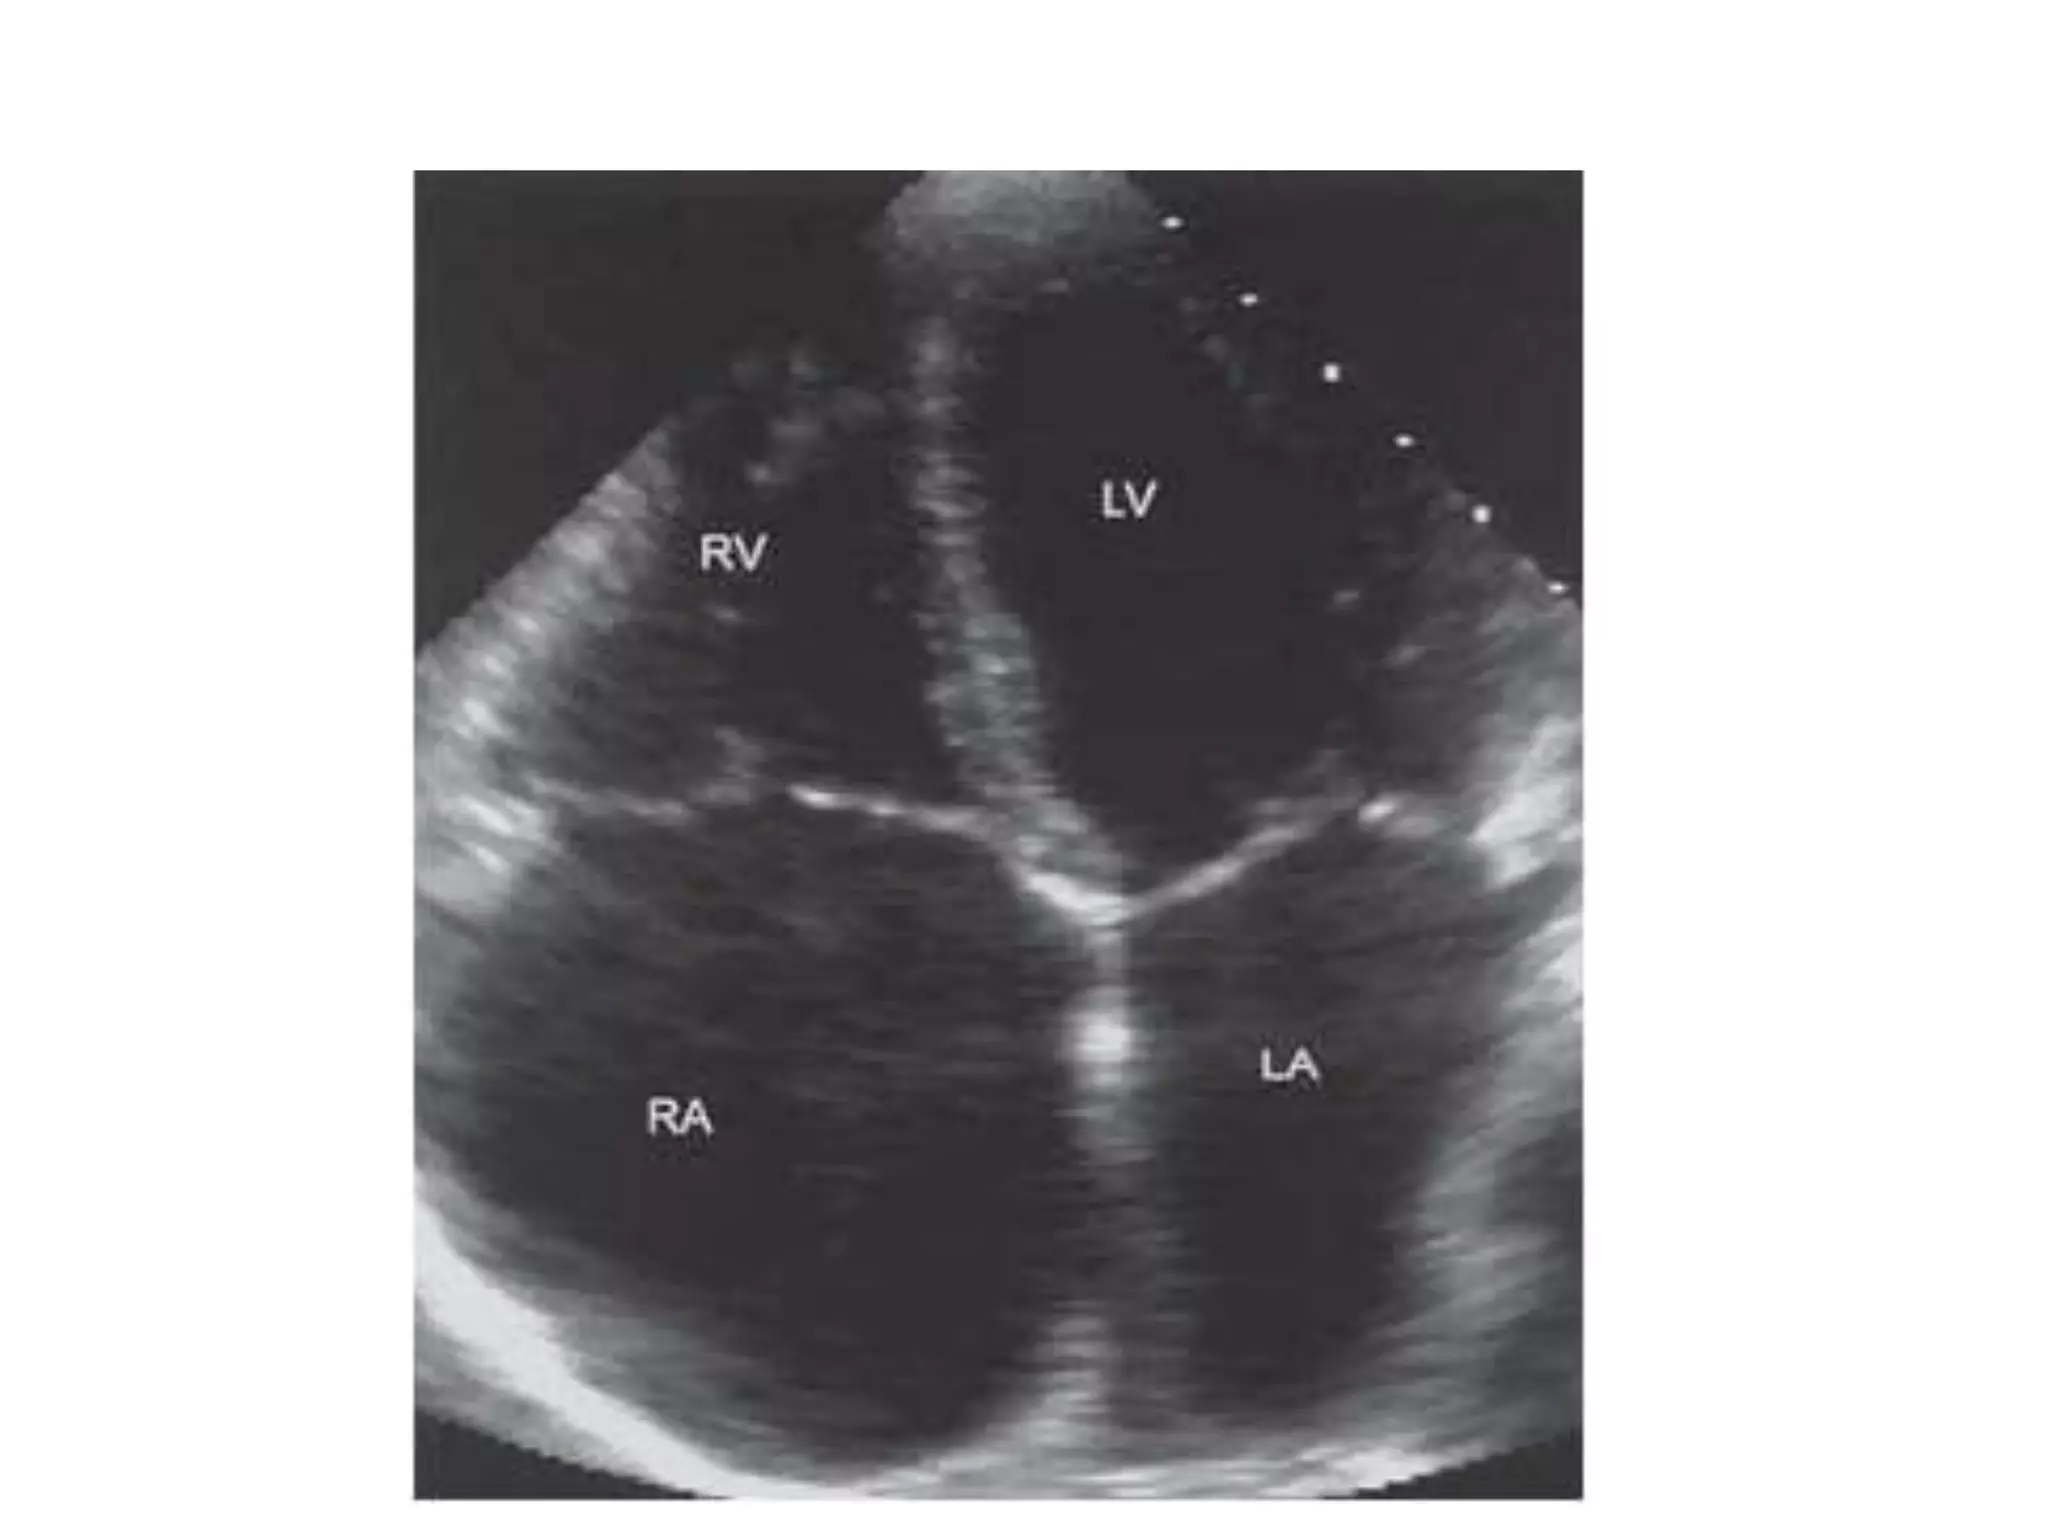

Sub–Costal 4 Chamber View(SC4CH)

1. Transducer position: under the

xiphisternum

2. Marker dot position: points towards left

shoulder.

3. The subject lies supine with head slightly low (no pillow). With

feet on the bed, the knees are slightly elevated

4. Better images are obtained with the abdomen relaxed and

during inspiration

5. Interatrial septum, pericardial effusion, desc abdominal aorta

Sub–Costal 4 ChamberView(SC4CH) 1. Transducer position: under the xiphisternum 2. Marker dot position: points towards left shoulder. 3. The subject lies supine with head slightly low (no pillow). With feet on the bed, the knees are slightly elevated 4. Better images are obtained with the abdomen relaxed and during inspiration 5. Interatrial septum, pericardial effusion, desc abdominal aorta